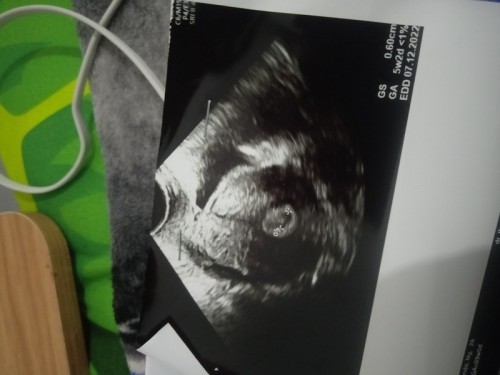

Bun mau tanya , saya di nyatakan hamil stlh USG UK 5week 2 day . Sblmnya sy penderita PCOs kanan kiri . Sy tespek selalu garis 1 tapi ktika tespek pakai merek akurat hasilnya garis dua samar sekali harus di senter . Kmrin sy d beri penguat kandungan berupa peluru untuk di masukkan ke Anus . Dan ini hasil USG sy . Apakah ada yg sprti sy bun . Dan kira2 kantung kehamilan sy normal atau tidak .. katanya klw tespek negatif bisa JD hamil kosong/BO sy sangat khawatir Bun ini kehamilan pertama sy . #seriusnanya #bantusharing #ingintahu #pleasehelp #firstbaby #firstmom